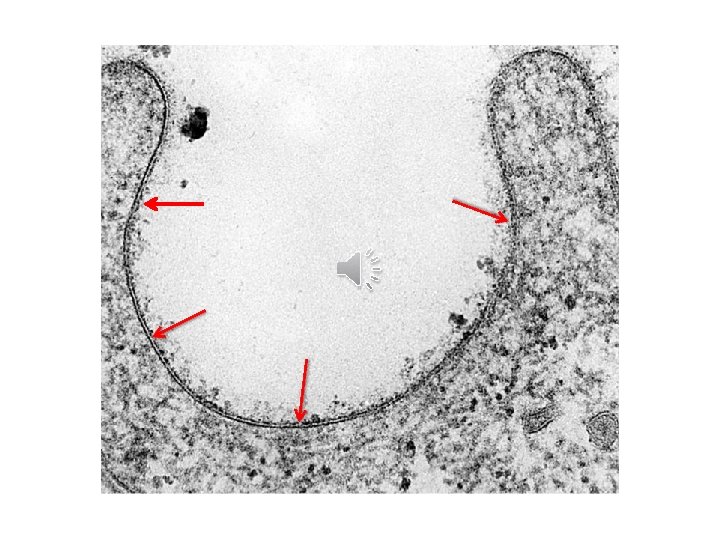

Cell membrane • Cell membrane = plasma lemma: • Membranous cytoplasmic organelle concerned with cell covering (7. 5 -10 nm thickness). • LM: not seen (except with silver and PAS). • EM: a trilamellar membrane (3 layers): dark - light dark.

Cell membrane: functions 1. Phagocytosis: engulfing solid materials (phagosomes) in. 2. Pinocytosis: engulfing fluid materials (pinocytic vesicles) in. 3. Exocytosis: expulsion of residual bodies out. 4. Passive diffusion (with concentration gradient): for gases, ions. 5. Active transport (against concentration gradient by using energy of ATP): for ions, amino acids. 6. Selective transport (through binding material with receptors present on glyco-calyx): for viruses, drugs, hormones. . .